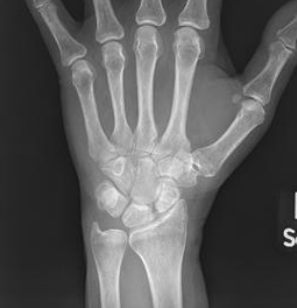

What are seen on xray for a SLAC stage 3 wrist?

Pa radiograph

What are seen on a lateral xray for a SLAC wrist